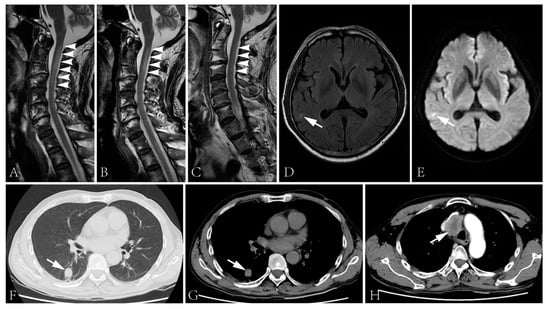

Figure 2.

(A–C) Spinal cord MRI showed T2 signal abnormality in the cervical cord at first admission (A), two days after the initiation of intravenous glucocorticoid (B) and second admission (C). The spinal cord lesion shortened after the administration of intravenous glucocorticoid and was merely visible during the second admission. (D,E) T2 flair (D) and DWI (E) images of the brain showed right temporal lobe hyperintensity. (F–H) The CT scan showed a lung lesion (F,G) and a mass lesion with enhancement in the superior mediastinum (H).

Blood glucose, HbA1c, folic acid and vitamin B12 values were within their normal range. HIV and syphilis screening results were negative. Immunoglobulin light chain and monoclonal immunoglobulin was not detected in blood and urine samples. ANA was positive (1:100). Anti-dsDNA, ENA and ANCA antibodies were all negative. T-SPOT.TB, G and GM tests were all negative. The CSF protein level was 928 mg/L (normal range: 120–600 mg/L) with a slightly elevated WBC count (14 × 106/L, normal range: 0–8 × 106/L). The IgG index analysis demonstrated mild blood–brain-barrier impairment. CSF-restricted oligoclonal bands were detected. CSF cytology demonstrated no malignancy. Anti-NF186 and anti-CV2/CRMP5 antibodies were detected using cell-based assays (Figure 1, anti-NF186 1:32; Anti-CV2/CRMP5 1:100), which were further verified by immunodot blot assay. Anti-AQP4, anti-MOG, anti-ganglioside and other paranodal and paraneoplastic antibodies were not detected. Spinal cord MRI examination showed a cervical cord lesion (Figure 2A). The brain and brachial plexus MRI results were normal. The electrophysiological exam showed a mixed demyelinating and axonal polyneuropathy (see Table S1 in Supplementary Material). PET-CT results revealed a small pulmonary nodule and a mediastinal lymph node with increased FDG metabolism.

Intravenous immunoglobulin was administrated (0.4 g/kg/d × 5d), followed by intravenous methylprednisolone (160 mg/d × 5d, tempered to 80 mg/d × 5d). The numbness of his four limbs and weakness of his upper limbs were alleviated post-treatment. The sensory disturbance level descended to T10. The muscle strength increased to 4+ in his proximal upper limbs and 4 in distal upper limbs. Moreover, micturition and defecation disturbances improved. The lesion in the cervical cord improved (Figure 2B). However, the biopsy of the lung lesion and lymph node were rejected. He was discharged with oral prednisone, 40 mg/d.

The patient was admitted again three days after being bedbound. His muscle strength was graded 0 in the lower limbs, and the sensory disturbance elevated to T2 level. Other neurological examinations were similar to the first admission. Epileptic attacks were not observed. The anti-NF186 antibody was undetectable but the anti-CV2/CRMP5 antibody was still detected. The CSF protein level was 497 mg/L (normal range: 120–600 mg/L) with a normal cell count. MRI examination revealed a cervical cord lesion and a brain lesion of the right temporal lobe without prominent enhancement (Figure 2C–E). No further evidence of thromboembolic stroke or metastasis was detected. The pulmonary nodule prominently enlarged and a mass lesion with enhancement was observed in his superior mediastinum by CT scans (Figure 2F–H).